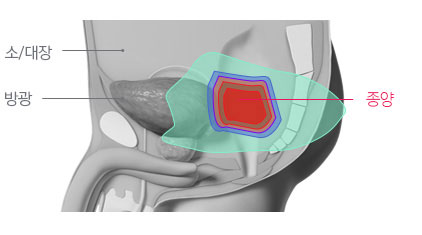

엑스선치료로는 고선량 치료가 어렵고, 부작용이 흔함.

이미 방사선치료가 시행된 재발 직장암의 경우 종양 제거가 어렵고, 수술의 경우 미용적, 기능적 제한이 큰 것으로 알려져 있습니다. 따라서 고선량의 방사선 재 치료가 시행되는 경우가 많은데, 이 경우 세기조절 방사선치료를 시행하더라도 주변 정상 장기에 노출되는 방사선으로 인한 부작용이 흔하며, 총 방사선량이 제한되어 5년 종양 제어율이 50% 이하로 알려져 있습니다. 하지만 주변 정상 장기에 방사선 노출을 크게 낮출 수 있는 양성자치료는 부작용에 대한 우려를 낮추면서 고선량의 방사선을 전달하여 종양을 제거할 수 있을 것으로 기대하고 있습니다.